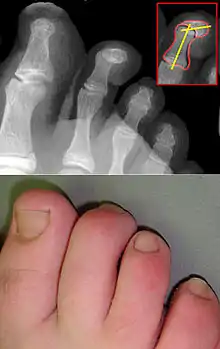

Молоткообразная деформация пальцев стопы

Молоткообразная деформация пальцев стопы (молоткообразные пальцы) — это деформация второго и третьего пальца стопы. Пальцы приобретают форму молоточка. Молоткообразная деформация пальцев стопы — это следствие сложной общей деформации стопы. Данная деформация возникает вследствие нарушения натяжения сухожилий мышц-сгибателей, а также из-за снижения подвижности межфаланговых суставов пальцев стопы. При снижении активности пальцев суставы как бы фиксируются в согнутом состоянии.[1]

Очень часто молоткообразная деформация пальцев сопровождается такими ортопедическими патологиями как: вальгусная деформация большого пальца, поперечное плоскостопие, церебральный паралич, полиомиелит, миелодиспластическая полая стопа и др. Данная деформация стопы опасна таким осложнением, как развитие отстеоартроза вследствие подвывиха фаланг пальцев. Также при этом недуге образуются большие мозоли и натоптыши из-за сильного давления и постоянного трения обуви.